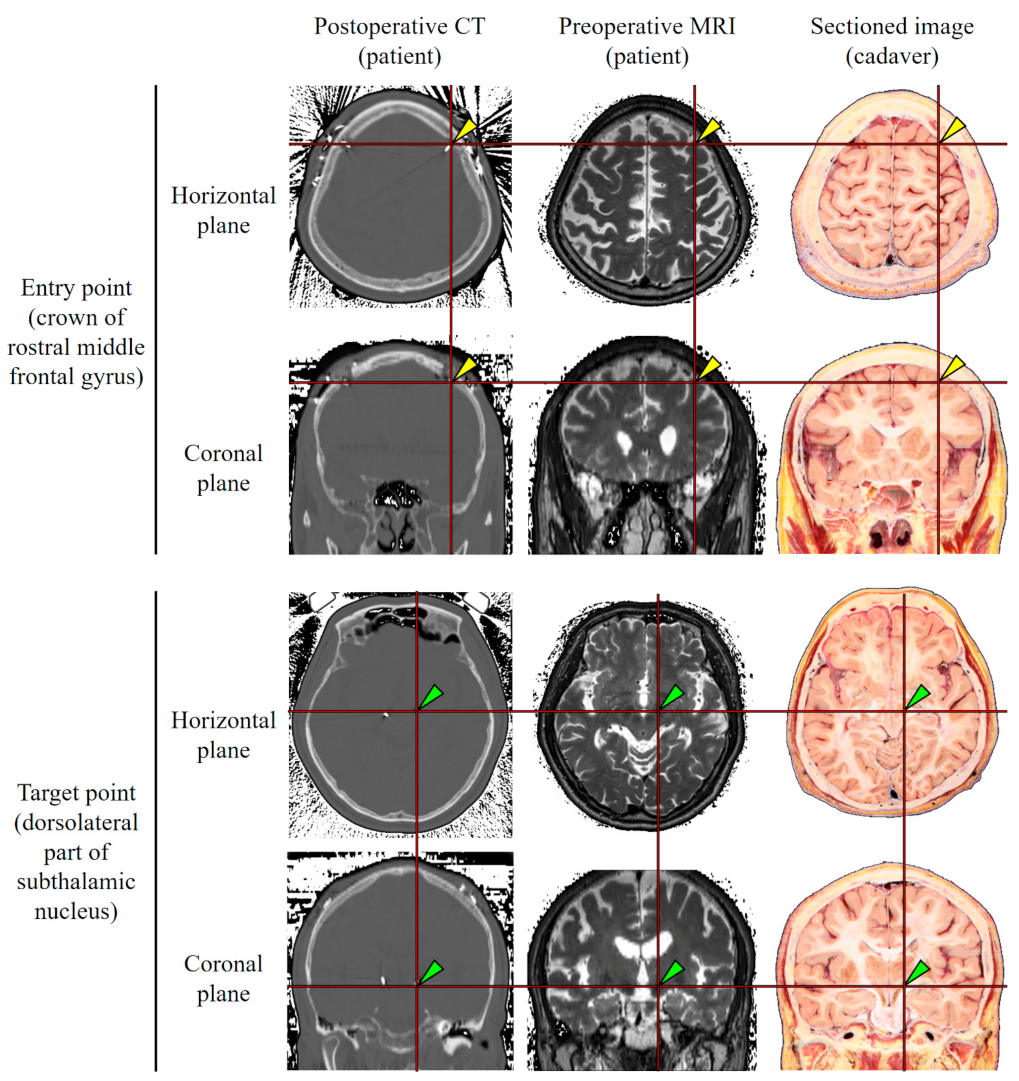

In the 31 patients, the entry point was the crown of the rostral middle frontal gyrus underneath the frontal bone. The target point was the dorsolateral part of the subthalamic nucleus. The entry and target points were indicated on the sectioned images so as to produce a virtual DBS electrode on the volume model (Figure 1).

The entry point (crown of the rostral middle frontal gyrus) and target point (dorsolateral part of the left subthalamic nucleus) obtained from 31 patients’ MRIs were marked on the horizontal, coronal, and sagittal planes on the real color volume model through the registration. On average, the entry point was located at +50.5 mm in the horizontal plane, +26.0 mm in the coronal plane, and +32.0 mm in the sagittal plane on the anterior commissure–posterior commissure (AC-PC) coordinates. Around the entry point, the superior frontal sulcus, where surgical accidents are likely to occur, could be seen. The target point was located at −6.5 mm in the horizontal plane, −4.5 mm in the coronal plane, and +10.0 mm in the sagittal plane on the AC-PC coordinates. Around the target point, care should be taken when passing the optic tract and posterior cerebral artery. The entry and target points corresponded well with the postoperative CTs of the 31 patients (Figure 3).

The real color volume model enables observations of minute anatomical structures. It can be difficult for medical students to identify deep brain structures in gray scale images of an MRI or CT. By virtue of the real color of the volume model, medical students can be familiar with the sectional brain’s anatomy before they study DBS surgery. In the case of neurosurgeons performing DBS surgery, misplacement of the DBS electrode on the medial lemniscus or substantia nigra can result in various adverse effects. Even within the subthalamic nucleus, its motor, limbic, and associative subdivisions have different functions [23,24]. Therefore, neurosurgeons interpret preoperative MRIs of patients to plan the DBS approach and perform an actual cadaver dissection to grasp the detailed anatomy of the deep brain [10]. These minute structures of the deep brain can be observed on the real color volume model, owing to the voxel size of 0.5 mm × 0.5 mm × 0.5 mm. The real color volume can be helpful in associating the actual cadaver to medical images of patients (Figure 1).

Figure 1. Entry point (yellow arrow head) and target point (green arrow head) of DBS. The entry point and target point acquired from the post-operative CT of a DBS patient as a representative were applied to the pre-operative MRI of a DBS patient through registration. The entry point and target point on the pre-operative MRI of a DBS patient were applied to the sectioned images of a cadaver by comparing the anatomy of the brain structures.